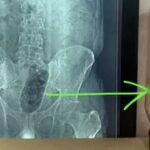

सरगुजा जिले के दरिमा थाना क्षेत्र के छिंदकालो गांव में एक अजीबोगरीब घटना सामने आई है। 35 वर्षीय युवक की मौत का कारण जानने के लिए जब पोस्टमार्टम किया गया, तो डॉक्टर भी हैरान रह गए। मृतक के गले में एक जिंदा मुर्गा फंसा हुआ मिला।

परिजनों ने युवक को अस्पताल लाते समय दावा किया था कि वह गिरने की वजह से घायल हुआ है, लेकिन पोस्टमार्टम में चौंकाने वाला खुलासा हुआ। डॉक्टरों के अनुसार, मुर्गा निगलने के प्रयास में उसका गला पूरी तरह से बंद हो गया, जिससे दम घुटने से उसकी मौत हो गई।

“मैंने अपने करियर में करीब 15 हजार पोस्टमार्टम किए हैं, लेकिन इस तरह का मामला पहले कभी नहीं देखा। यह घटना बेहद असामान्य और चौंकाने वाली है।”